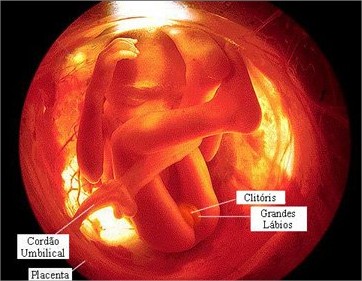

O bebê com 19 semanas de gestação provavelmente já chegou a 15 cm e 240 gramas mais ou menos. Você sabia que 90% do líquido amniótico que envolve o bebê é urina? Sim, ele já treina engolindo líquido e fazendo xixi!

Sem contar que o mecônio já começou a se formar1. Mecônio é aquele cocô bem escuro que o bebê faz depois de nascer. Nesta semana seu rosto está cada vez mais definido, suas sobrancelhas e cílios começam a aparecer, assim como os seus pequenos fios de cabelo.

Suas pálpebras já estão totalmente formadas e cobrem seus olhos que ainda não consegue abrir e fechar, mas são plenamente sensíveis à luz. Suas mãos, que já possuem dedos formados inclusive com unhas, já se abrem e fecham.

Nas 19 semanas de gravidez, os ossos dos ouvidos estão em fase final de desenvolvimento. Por isso, ele já consegue escutar ruídos e sons externos, inclusive a voz dos papais. Seu órgão genital também já está totalmente formado2 e, no caso de uma menina, todo seu sistema reprodutor como o útero já está no local correto.

Nas 19 semanas de gravidez, os ossos dos ouvidos estão em fase final de desenvolvimento. Por isso, ele já consegue escutar ruídos e sons externos, inclusive a voz dos papais. Seu órgão genital também já está totalmente formado2 e, no caso de uma menina, todo seu sistema reprodutor como o útero já está no local correto.